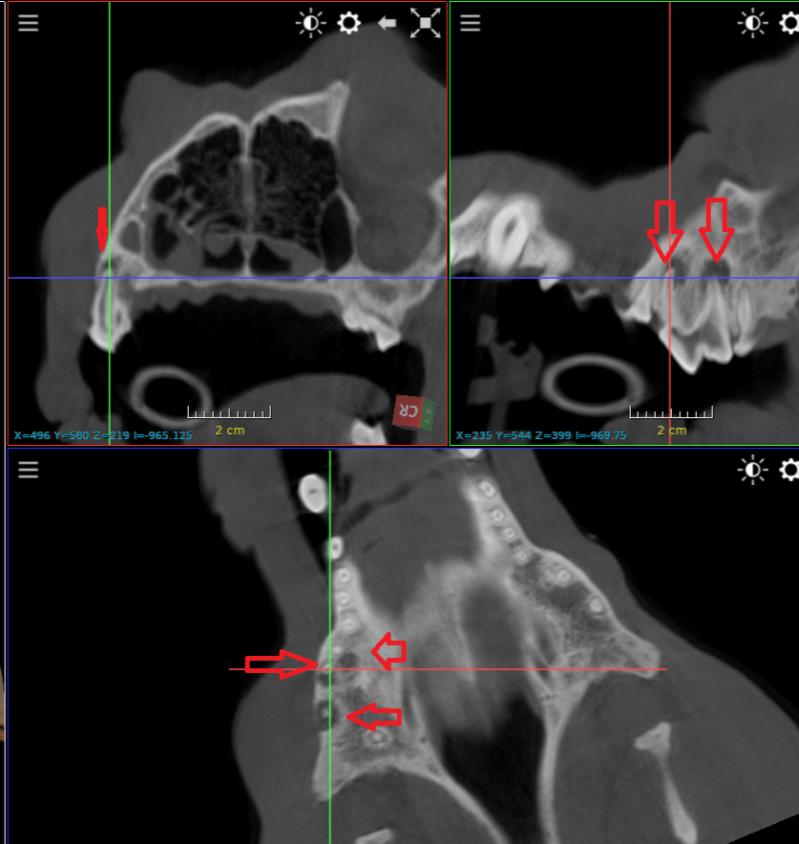

Omdat we nu een Ct scanner hebben kunnen we een extra dienst aanbieden bij de tandverzorging van honden en katten.

De Ct scanner maakt een driedimensionale beeld van heel het gebied in 20 seconden. Daardoor kunnen we op zeer korte tijd alle tanden beoordelen op aanwezigheid van beenresorptie en tandwortel ontsteking.  Een tand die er op het eerste zicht normaal uitziet kan in de wortel ernstig ontstoken zijn.

Voorbeelden van verdoken tand problemen . Op radiografie zie je wat zich onder het tandvlees afspeelt.